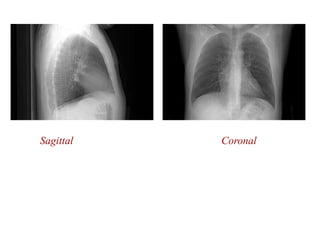

Sagittal Coronal

Projection X-Ray Disadvantage: Depthinformation lost Advantage: Cheap, simple ) z ( f ) , , ( μ density electron , z y x  attenuation coefficient Measures line integrals of attenuation    )dl μ( o d I I x,y,z e Film shows intensity as a negative ( dark areas, high x-ray detection